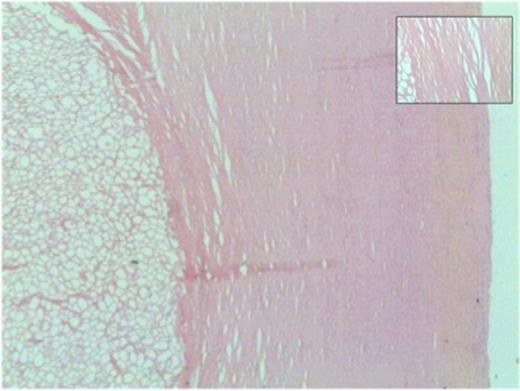

Microscopically, both nodules showed similar histological features. The larger nodule required prolonged, gentle decalcification before reasonable tissue sections could be obtained. Each had a thick shell of dense paucicellular collagen arranged as concentric layers with only a few fibroblasts and inflammatory cells present peripherally (Figures 4b and 5). The shell was devoid of cartilage and it encased necrotic adipose tissue (Figure 6) in which there was focal dystrophic calcification. No granulomatous inflammation, lung parenchyma, abscess formation, caseous type necrosis or neoplasm was identified.

Thick shell of paucicellular collagen surrounding necrotic fat (40x magnification). Inset: Closer view of concentrically arranged thin layers of collagen

Necrotic adipose tissue centrally within the nodule (200x magnification)